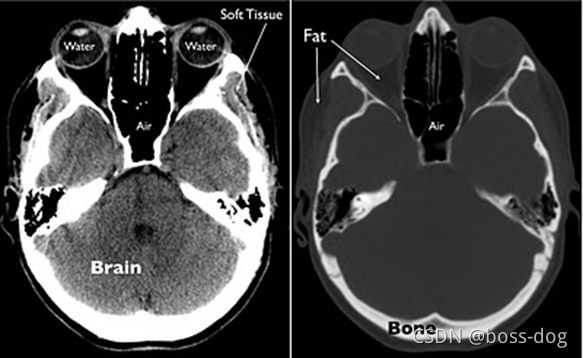

像CT的话,窗口很宽,从负一千到正一千,如果全部显示出来的话,人眼不一定能够把那些细节检测出来看出来,所以针对CT,可以调整图像。

上图所示,左图中,我们的目的是将软组织显示清除,其他的如骨头、空气等等不需要看的那么清楚,于是就可以使用Soft Tissue窗口;右图中,如果想看清楚如有些骨折或者有一些异常的关于骨头的,就可以使用Bone窗口。

可以局部的或者针对某个区域、某个具体的组织,在显示方面可以进行优化。